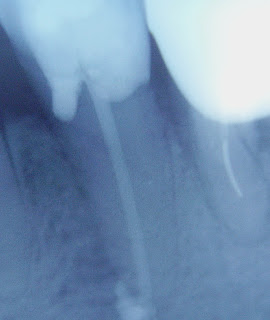

Случай на субпериостален абсцес с некроза на пулпата при 14 годишно момиче. Случаят е показан в раздел Ендодонтия на блога през Февруари 2009 год. Ето и отличният резултат от лечението 19 месеца след кореновото лечение. Вижда се пълното възстановяване на костната структура и на периодонталния лигамент само шест месеца след лечението и запазването на постигнатото пълно оздравяване 19 месеца след лечението.Снимките са съответно преди и веднага след лечението в рамките на едно посещение. Контролите са направени след една седмица, три седмици, шест месеца и деветнадесет месеца.

Случай на пулпит на долен ляв осми зъб. Снимките са преди лечението, веднага след запълване на каналите в едно посещение и две години след лечението. Виждате идеалното здраве на периапикалната кост и пълна липса на периапикални изменения след период от две години.

Трети случай - касае се за субпериостален абсцес на долен ляв втори премолар. Търсейки канала колегата е направил перфорация под нивото на костта и е изпилил по-голямата част от тъканите на коронковата част на зъба. Виждате състоянието на зъба преди моето лечение, веднага след запълването на канала,седем седмици по-късно и две години след лечението. Налице е пълно възстановяване на коста около апекса на зъба и липса на клинична симпотматика.

На долните две снимки можете да видите крайния резултат от запълването. Забележете извивката на единия от каналите в последните милиметри и доброто запълване с биокерамична паста на тази част.

На долните две снимки можете да видите крайния резултат от запълването. Забележете извивката на единия от каналите в последните милиметри и доброто запълване с биокерамична паста на тази част.